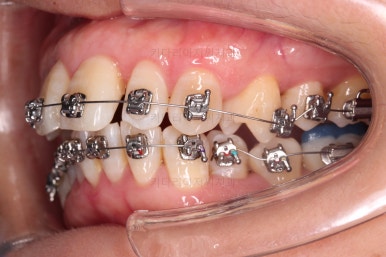

초진 시, 입안의 모습이에요.

"최근 들어 점점 틀어지고, 점점 튀어나오고, 점점 사이가 벌어져요."

성장이 끝난 성인들은 해가 갈수록 특히 아래앞니가 삐뚤어지는 것은 자연스러운데요.

이번 환자분의 말씀대로 최근에 변하가 심하게 나타난 경우는 원인이 딱 하나에요.

잇몸(치주)

흔히 풍치라고 하죠.

전반적인 잇몸이 나빠진다 -> 어금니가 씹는 힘에 버텨주지 못하고 앞으로 쓰러진다. -> 앞니가 강하게 부딪히며 아래앞니가 윗니를 앞으로 쳐낸다. -> 돌출입이 생기고, 앞니 사이 틈새가 생긴다.

앞니가 튀어나오고 틈새가 생기는 것이 결과이긴 하지만 원인은 어금니쪽 잇몸에서부터 찾아야해요.

이번에 사용하신 장치는 엠파워 메탈이라고 하는 자가결찰 금속 장치인데요.

금속 재료를 시각적으로 신경쓰지 않으셔꼬 메탈장치가 세라믹에 비해 양치라던지 잇몸에 그래도 약간의 장점이 있어서 추천되기도 했어요.